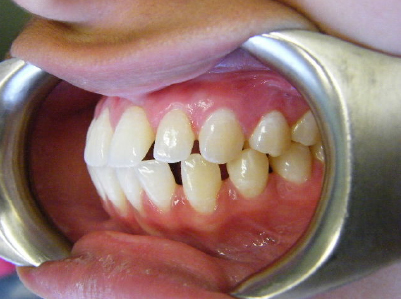

Patient 2: Significant increased overjet and upper and lower crowding.